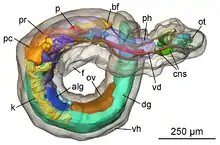

3D Reconstruction of medical images

Clinical routine of diagnosis, patient follow-up, computer assisted surgery, surgical planning etc. are facilitated by accurate 3D models of the desired part of human anatomy. Main motivation behind 3D reconstruction includes

- Improved accuracy due to multi view aggregation.

- Detailed surface estimates.

- Can be used to plan, simulate, guide, or otherwise assist a surgeon in performing a medical procedure.

- The precise position and orientation of the patient's anatomy can be determined.

- Helps in a number of clinical areas, such as radiotherapy planning and treatment verification, spinal surgery, hip replacement, neurointerventions and aortic stenting.